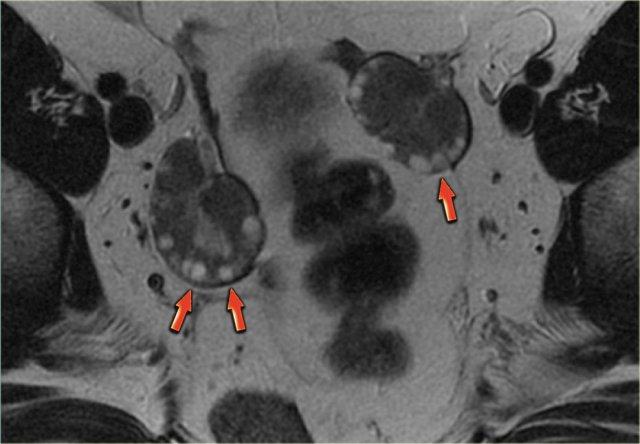

Các hình ảnh siêu âm cho thấy nhiều tổn thương buồng trứng phải đơn giản và một tổn thương phức tạp (mũi tên đỏ).

Tổn thương sau biểu hiện hồi âm mức thấp lan tỏa và không có tín hiệu dòng chảy trên Doppler.

Lưu ý có xuyên âm tốt (mũi tên xanh).

Các đặc điểm này gợi ý sự hiện diện của nang xuất huyết.

Tiếp tục xem các hình ảnh MRI.

Các hình ảnh siêu âm cho thấy buồng trứng phải và trái: ở cả hai bên đều có hình ảnh trông giống như tổn thương đặc.

Tuy nhiên, có xuyên âm tốt, gợi ý chúng ta có thể đang đối mặt với các nang xuất huyết.

Trên siêu âm Doppler (không hiển thị) không có mạch máu.

Tiếp tục xem kết quả MRI.

Trên hình ảnh chuỗi xung T1W mặt cắt ngang, cả hai tổn thương đều tăng tín hiệu, gợi ý mỡ, máu hoặc dịch giàu protein.

Kỹ thuật xóa mỡ không làm giảm tín hiệu trong các tổn thương này.

Trong một hình ảnh có kỹ thuật xóa mỡ tổng thể tương đối tốt, điều này loại trừ u quái chứa mỡ và xác nhận gợi ý về dịch xuất huyết.

Trên hình ảnh chuỗi xung T2W mặt cắt ngang, cả hai tổn thương đều cho thấy hình ảnh ‘shading’ điển hình.

Sự sụt giảm dần dần tín hiệu T2 được cho là do sự kết hợp của độ nhớt tăng dần và nồng độ protein cùng sắt tăng dần về phía phần thấp của tổn thương.

Không có ngấm thuốc trên hình ảnh trừ (sau tiêm Gd trừ trước tiêm Gd).

Một lần nữa, kỹ thuật trừ rất hữu ích trong các trường hợp như thế này: sự tăng tín hiệu do Gd gây ra trên nền hình ảnh trước tiêm thuốc vốn đã rất sáng sẽ rất khó nhận biết nếu không có kỹ thuật này.